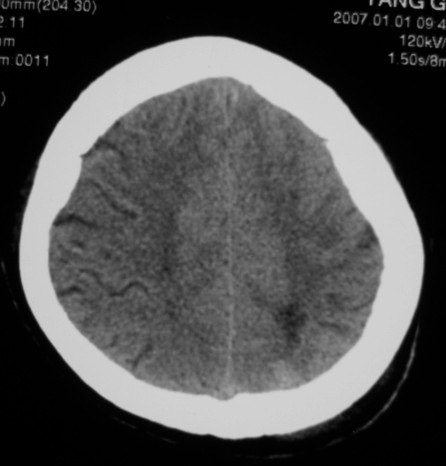

第一次ct片脑出血术后,出血吸收期。第二次ct 片左颞顶枕部及右颞顶部有脑回样高密度影。考虑珠网膜下腔出血。脑出血术后改变,脑出血恢复期 并脑积水。

第一次ct片脑出血术后,出血吸收期。第二次ct 片左颞顶枕部及右颞顶部有脑回样高密度影。考虑珠网膜下腔出血。脑出血术后改变,脑出血恢复期 并脑积水

脑炎;脑出血术后改变;脑积水。

两次的片都有,第二次比第一次的明显